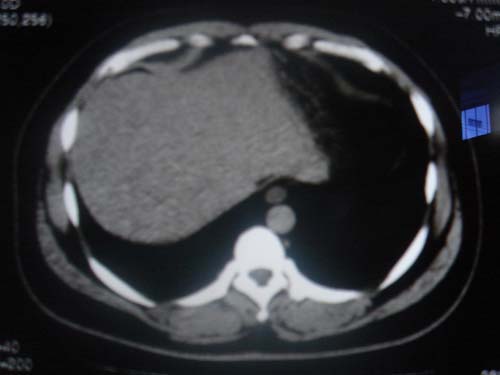

患者 男 40 右上腹不适 有胆囊息肉病史2年

最后二副图像示胆囊壁增厚,与肝分界欠清,建议强化ct或磁共振

片中示肝脏的ct值低于脾脏,肝脏右叶外缘部份凹凸不平,考虑脂肪肝,肝硬化可能。结合其检查如b超或ct增强检查。

胆囊未见明显异常,肝脏密度似比脾脏密度低,测量一下ct值排除一下脂肪肝.当然做一下增强或mr就更好了.

肝右叶密度不均,脾大。强烈要求增强扫描除外浸润型肝癌。

肝大   密度降低  脾大  脂肪肝?